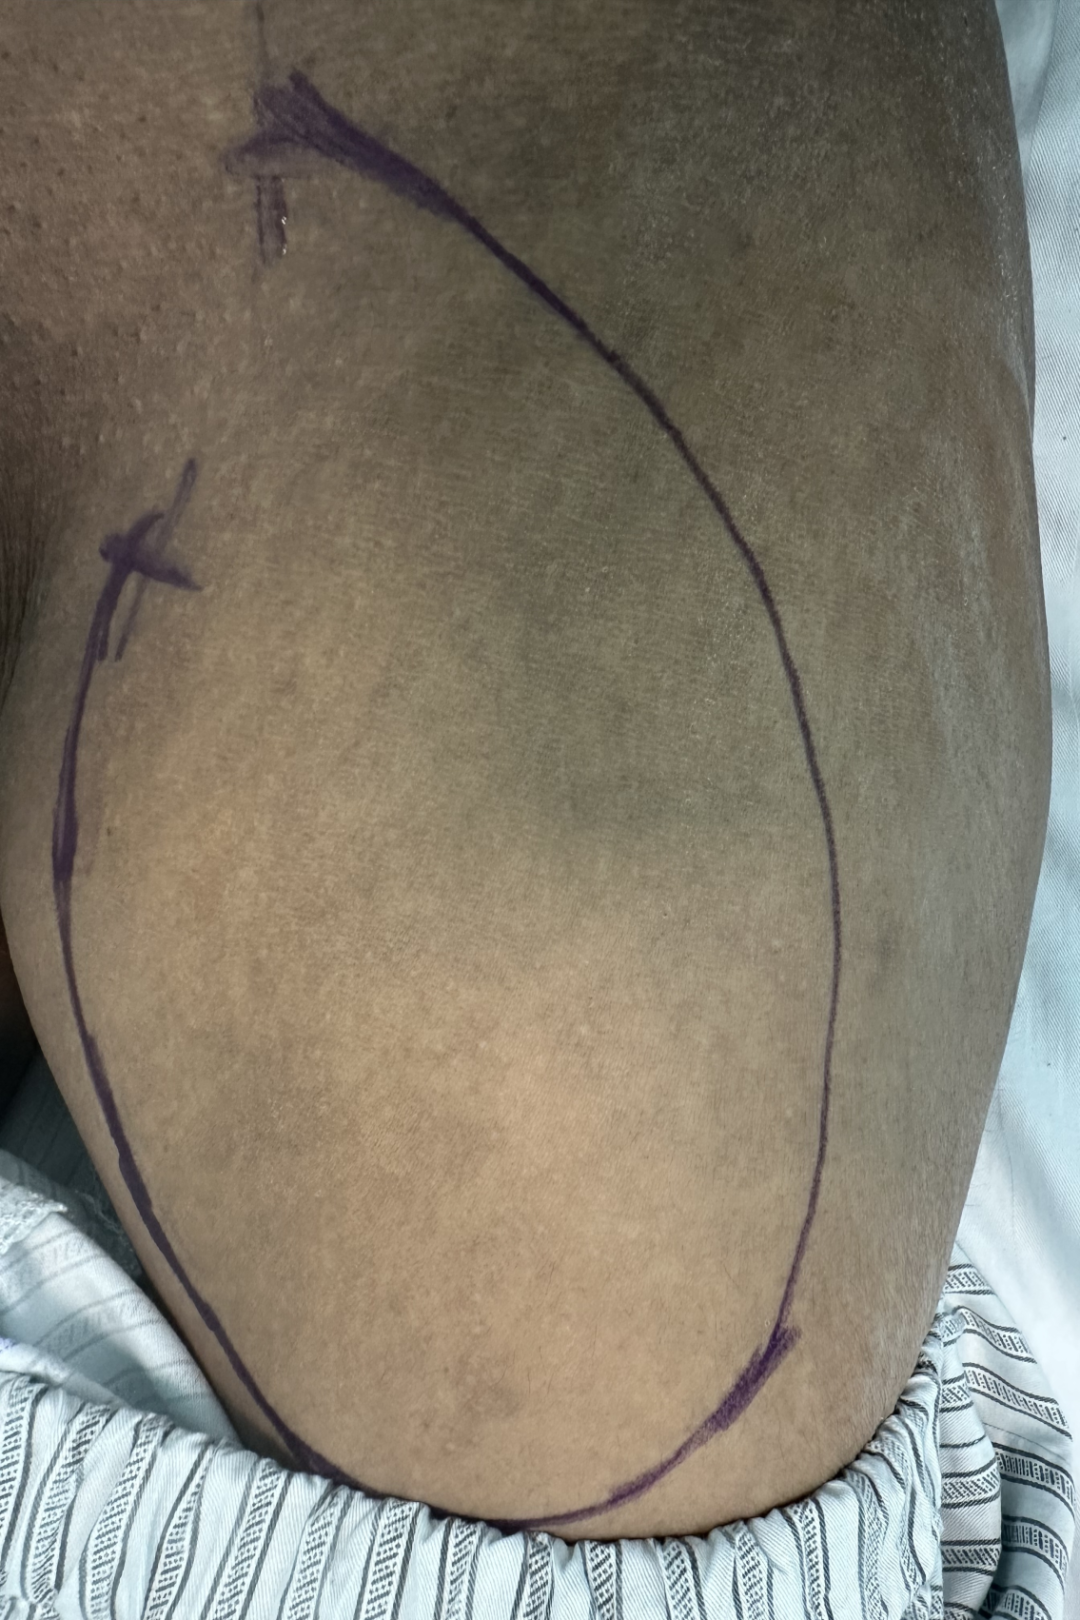

術前左側腹股溝標記擬置入人工血管位置